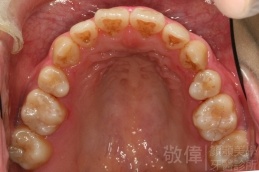

變臉矯正,原來戽斗妹跟大歪臉變成自信正妹

經由本院3D數影X光影像儀分析、與3D齒顎顏矯正技術,再配合口腔顎面正顎專科醫師施以正顎手術治療,雙方共同合作,使患者臉部外觀有很好的改善,大歪變小歪,產生了天南地北的大改變,她的人生也整個變得不一樣。

因為矯正與正顎手術的配合,使「戽斗妹」變成了「陽光正妹」,完全的改變了她的人生,在面對各種場合、與人交際都散發出自信微笑。所以,奉勸家長,如果小朋友有臉顎畸型的問題,應該考慮配合做這種簡單、安全、有效的正顎手術。

「3D齒顎顏矯正」,不止矯正您的牙齒,也會改變您的人生。「治療前」和「治療後」出社會的人生際遇一定會截然不同。